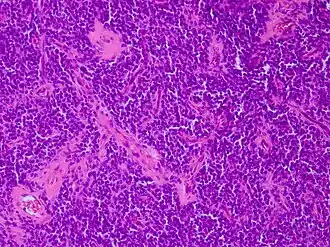

Coupe histologique colorée à l'hématoxyline et à l'éosine (H & É) d'une section de tumeur neuroectodermique primitive périphérique.

Les sarcomes d'Ewing, et plus généralement les tumeurs neuroectodermiques primitives (PNET), montrent une prolifération d'architecture diffuse, composée de petites cellules rondes au rapport nucléocytoplasmique élevé[5].